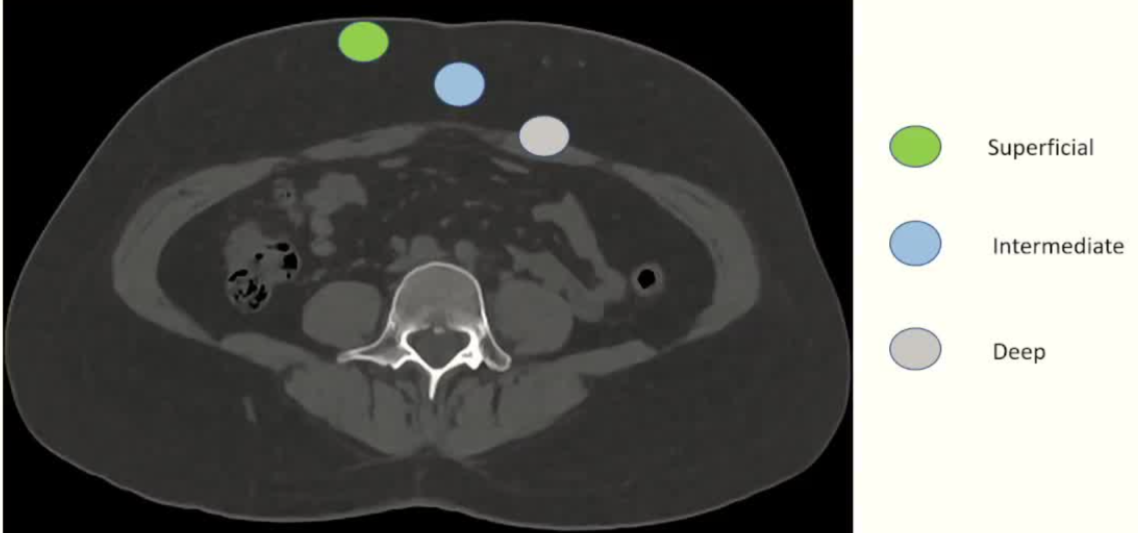

| 腹壁下病变 | MRI引导下 冷冻消融。装有热水的手套在皮肤表面保护皮肤 |

通常需要三根布针

隔离和布针

endomuscular

极少的安全余量

浅表性损伤和深层损伤在技术上更具挑战性(防护措施+++)